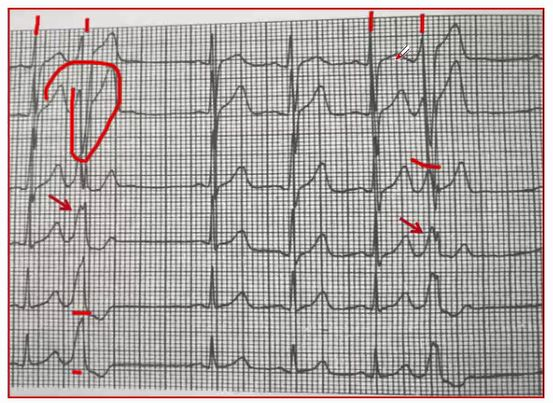

一、室性早搏心电图特点

1. 提前出现的宽大畸形(绝大多数)的QRS波(时限≥0.12s),其前无相关直立P波(室性融合波除外)。

余老师提醒大家:宽大或畸形,说明室性早搏的QRS波不总是宽大的,其时限也可以≤0.12s。

2. 少数情况下当室性期前收缩起源于高位心室时,可表现为与室上性QRS波稍有区别,但时限正常的QRS波。

3. 多数情况下无p波,少数情况下可以出现与QRS波相关的逆行p波。

4. 代偿间歇绝大多数为完全性代偿间歇,少数情况下为不完全代偿间歇。

5. 提前出现的宽大畸形的QRS波之间见到房室分离或室性融合波可确定为室性早搏。

6.继发性STT改变(室性期前收缩的T波和ST段与QRS波主波方向相反)。